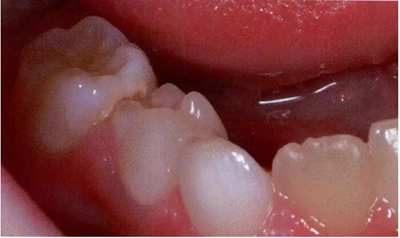

圖2:中度下沉的臨床像

遲發(fā)型乳牙下沉同時(shí)表現(xiàn)為下沉進(jìn)展及根吸收都很緩慢時(shí),通常可以保留的時(shí)間長(zhǎng)一些,甚或是不設(shè)期限地保留。處于一個(gè)并不擁擠的牙弓之中,伴有繼承恒牙胚先天缺失的輕中度下沉牙可以保留下來并修復(fù)高度以維持其功能。修復(fù)可以使用全覆蓋的樹脂高嵌體完成(圖7)。這種修復(fù)體能夠恢復(fù)下沉牙的合面高度,防止鄰牙傾斜以及對(duì)合牙伸長(zhǎng)。不過,我們很難預(yù)測(cè)這些牙齒什么時(shí)候脫落,還是會(huì)永久保留下去。與此相反,如果是發(fā)生在需要正畸的擁擠牙弓,那么就應(yīng)當(dāng)拔除這些牙;這一步應(yīng)當(dāng)只是作為正畸治療計(jì)劃的一部分來完成。

圖7:臨床照片顯示在一顆沒有繼承恒牙胚的下沉下頜乳磨牙上使用樹脂堆疊修復(fù)